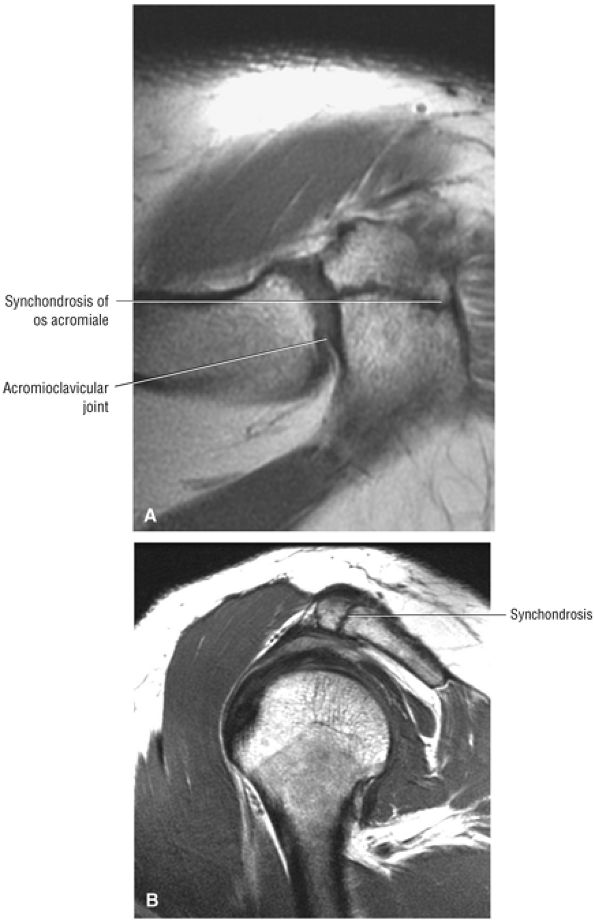

FIGURE 8.102 ● (A) The anterior undersurface of the acromion and the coracoacromial ligament form the coracoacromial arch. The subacromial subdeltoid bursa facilitates the passage of the rotator cuff and proximal humerus under the coracoacromial arch. (B) A superior axial image shows the anterior-to-posterior extent of the coracoacromial (CA) ligament perpendicular to the supraspinatus tendon. The fluid in the subacromial-subdeltoid bursa represents fluid between two serosal surfaces in contact with each other. One serosal surface is contributed by the undersurface of the coracoacromial arch and deltoid, and the other serosal surface is on the bursal side of the cuff.

|

![]() |

FIGURE 8.103 ● Pseudospur. The normal broad attachment of the coracoacromial ligament to the inferior surface of the acromion is shown on (A) T1-weighted coronal oblique and (B) sagittal oblique images. The low-signal-intensity acromial cortex (black arrows) and adjacent coracoacromial ligament and lateral slip of the deltoid attachment (white arrows) give the false impression of a small subacromial spur in the coronal plane. This pseudospur should not be misinterpreted as impingement; otherwise, unnecessary acromioplasties may be performed on patients with a normal coracoacromial ligament attachment and no associated acromial spurs.